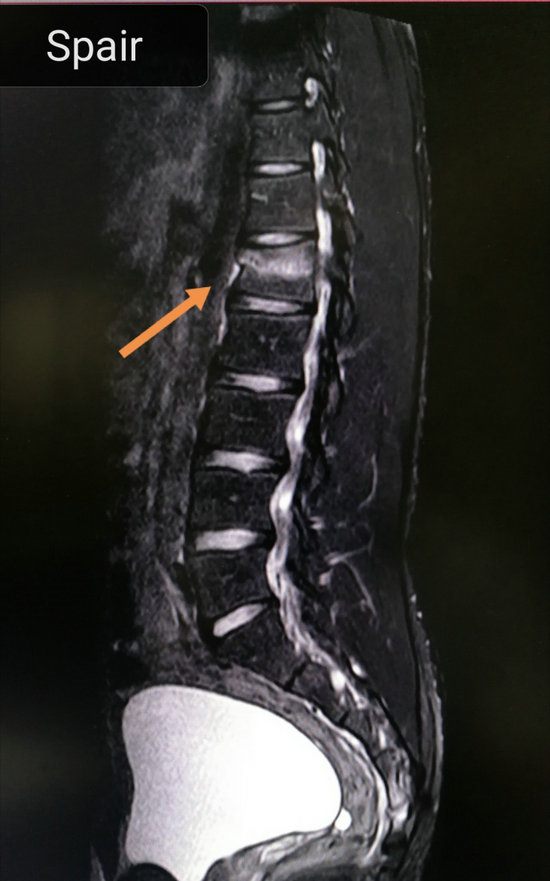

住院后骨科医生立即完善了MRI检查,发现胸12椎体为陈旧性压缩骨折,腰1椎体为新鲜压缩性骨折,在完善各项生化检查、心电图等检查的基础上,评估患者体质后,建议患者进行微创手术:经皮穿刺腰1椎体骨水泥成形术,这样患者能够快速康复、提高生活质量、减少并发症发生率,与患者及家属充分沟通病情及治疗建议后,患者及家属一致决定接受我们的建议。

胸腰椎压缩性骨折多发于下胸椎和上腰椎,有时不一定合并外伤史。患者主诉腰背痛,不敢活动,可妨碍站立行走。如果压缩程度较重,将会产生局部后凸畸形。压痛叩击痛常见,胸腰椎活动受限。胸腰椎压缩性骨折大部分为稳定骨折,少有脊髓损伤瘫痪者。X线或CT即可发现压缩骨折,但要确定是否为新鲜骨折,需再进行MRI检查。